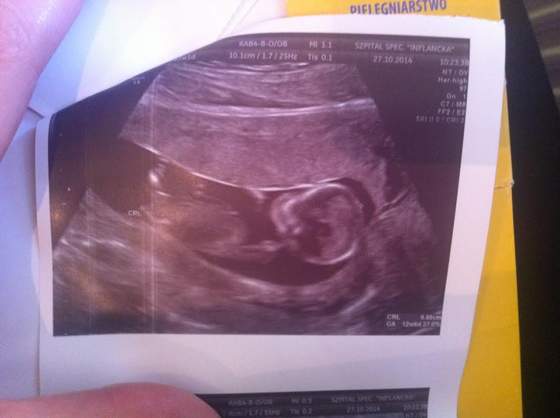

ma 7cm x1,5 cm (wcześniej miał 3,5cm nie wiem na ile, ale wiem na pewno ze to była wielka plama na szerokość) ale mam sie nim nie martwić, bo krwiak jest z dala od kosmówki czy tez łożyska (już nie pamietam) i nie zagraża wgl dziecku co było widać na usg, bo maluch spory już ma 6,9 cm serduszko wali jak dzwon